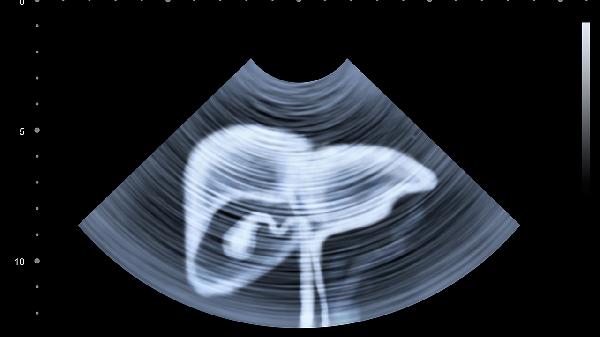

胆囊炎或胆石症可引起右上腹疼痛向右肩放射,急性发作时疼痛剧烈伴发热。高脂饮食易诱发胆绞痛。超声检查可明确诊断,轻度发作可解痉止痛,反复发作需考虑胆囊切除手术。